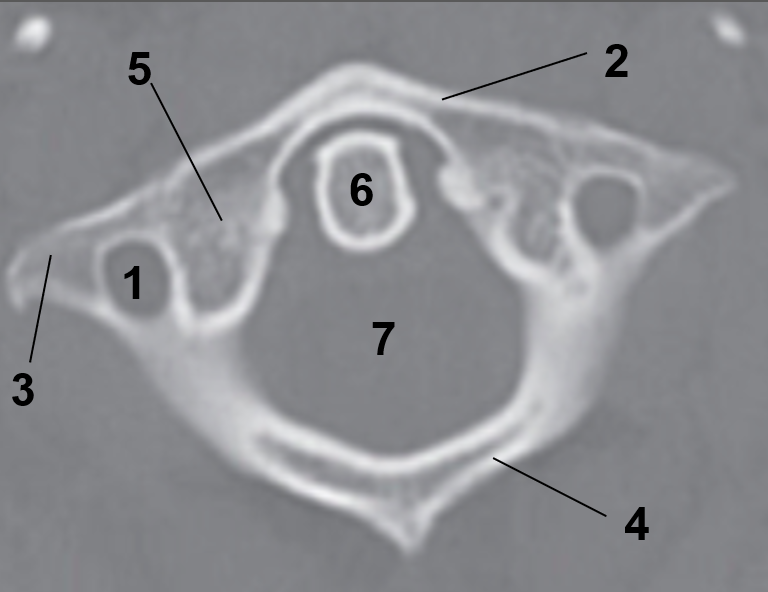

1?

Hard Palate

2?

Maxillary Bone

3?

Mandibular Rami

4?

Dens

5?

Transverse Foramen C1

6?

Spinal Cord

7?

Auricle

8?

Atlas